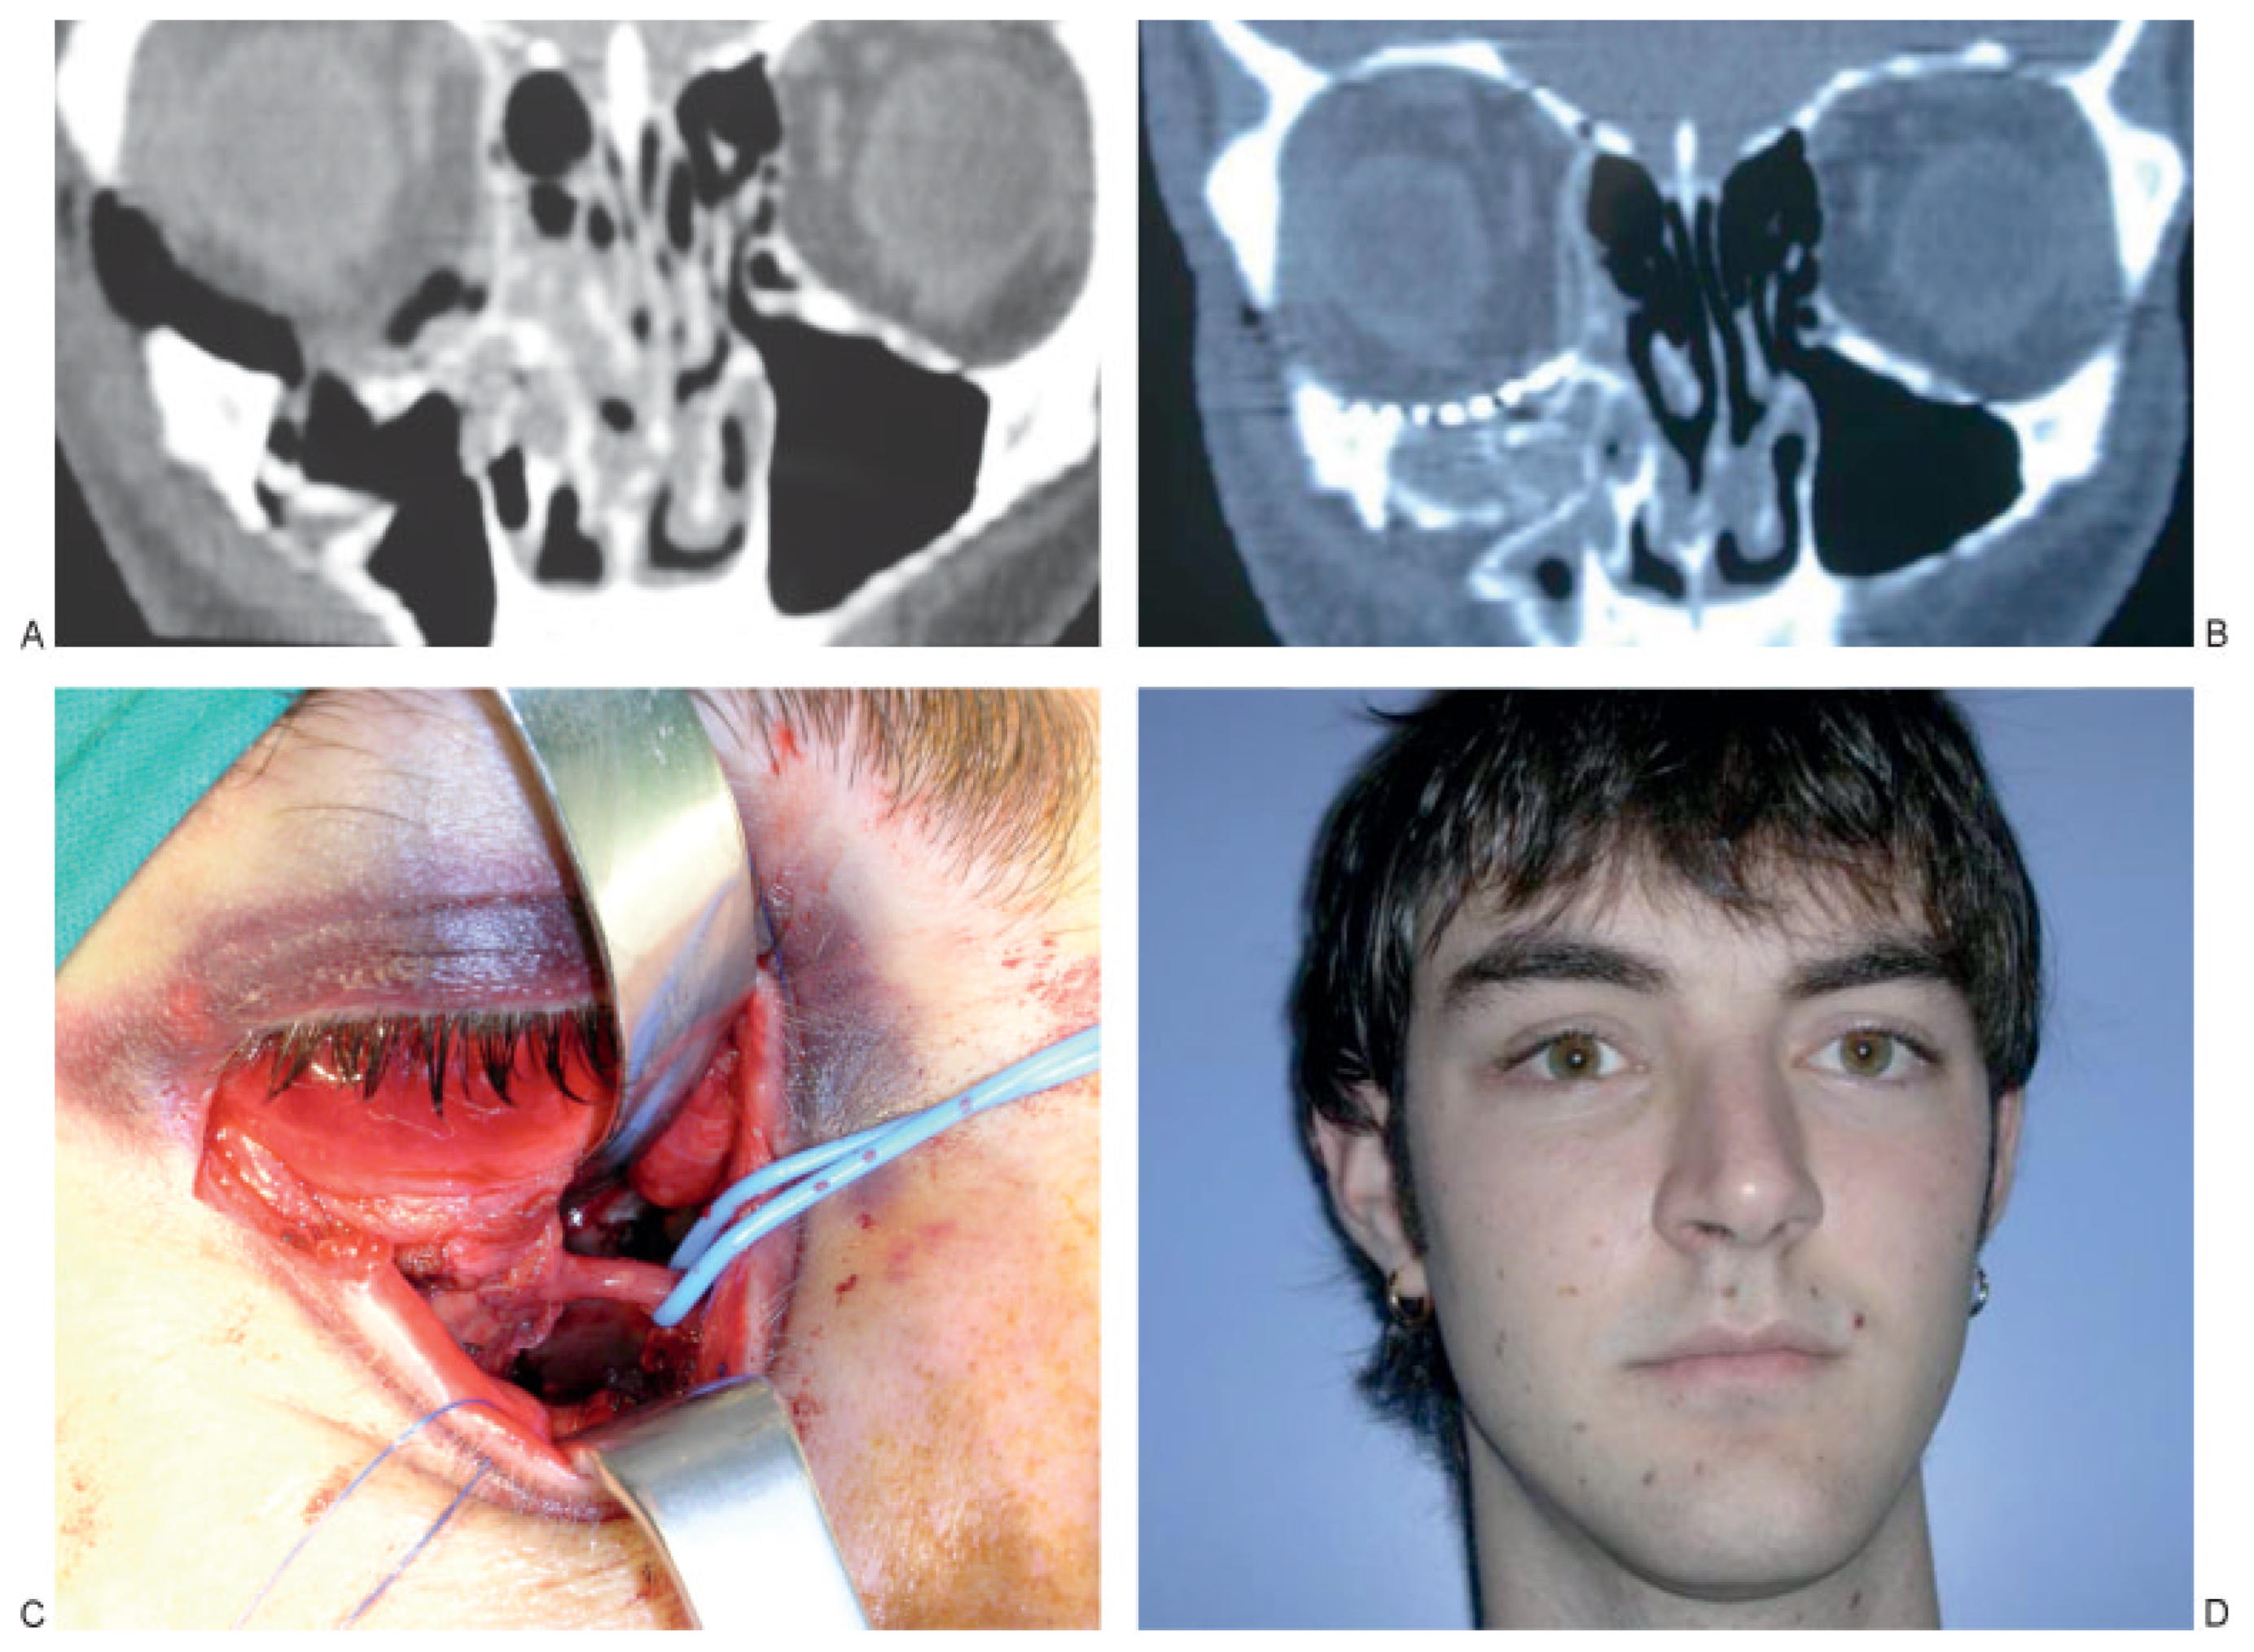

:SURGICAL TECHNIQUE

RESULTS